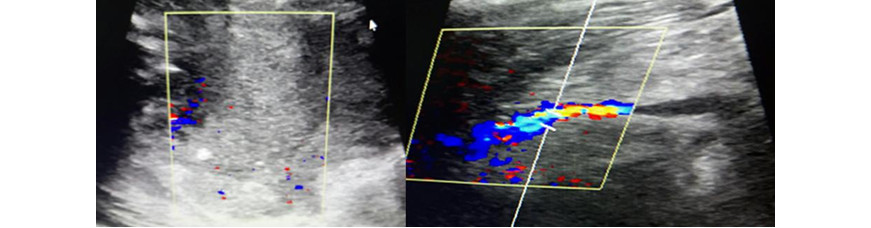

Volver a los detalles del artículo Sarcoma sinovial con invasión medular